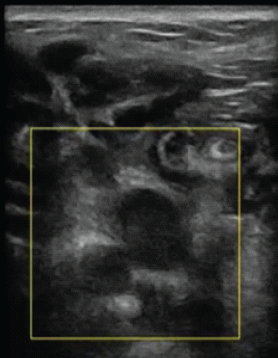

Soft-tissue Leiomyoma in a Rare Location: The Achilles Tendon

Abhishek Chaudhary , Akshay Shreegan , Mehar Dhillon , Animesh Saurabh , Sandeep Patel

………………………………p.94-98